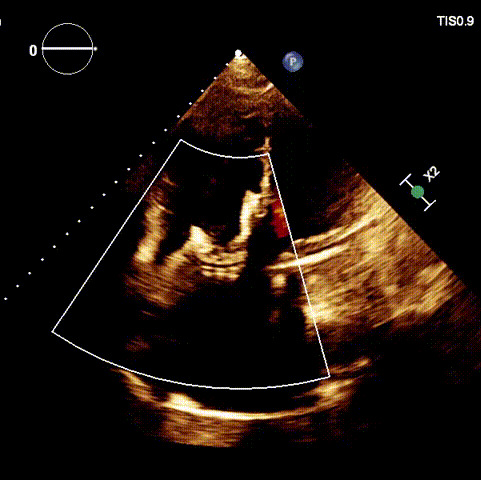

術(shù)后超聲

近日,廈門大學(xué)心血管病醫(yī)院王焱教授帶領(lǐng)的結(jié)構(gòu)性心臟病團(tuán)隊(duì),成功應(yīng)用LuX-Valve Plus經(jīng)血管三尖瓣置換系統(tǒng),為一例高危三尖瓣重度反流患者開展經(jīng)血管三尖瓣置換手術(shù)。此次手術(shù)系LuX-Valve Plus人工瓣膜在福建省的首例植入,手術(shù)過(guò)程順利,術(shù)后患者三尖瓣反流顯著改善,標(biāo)志著由葛均波院士團(tuán)隊(duì)作為主要研究者的LuX-Valve Plus經(jīng)血管三尖瓣置換系統(tǒng)全國(guó)多中心臨床研究的再一次成功實(shí)踐,為三尖瓣介入治療的醫(yī)學(xué)循證打下了夯實(shí)的基礎(chǔ)。 、